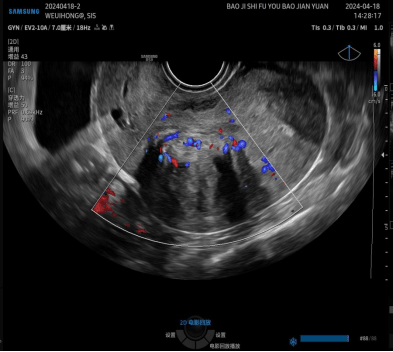

病例再现 / 01

二维超声显示肌瘤大部分位于肌壁间而不是宫腔内

宫腔水造影+三维超声显示肌瘤大部分凸向宫腔,仅有少部分位于肌壁间,二维超声不易观察到的宫腔粘连清晰可见。